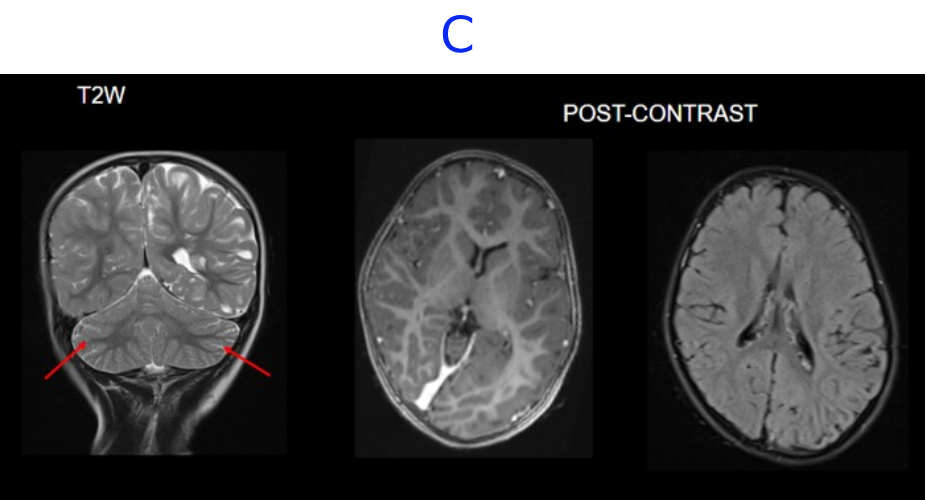

A. FINDINGS: MRI BRAIN WITH IV CONTRAST

• A. There is hemihemimegelencephaly in the left parieto-temporo-occipital lobes, characterized by enlargement of the involved hemisphere. There is associated gyral thickening with white matter signal changes in the adjacent subcortical white matter.

• B. Areas of rarefaction are seen in white matter signal changes. Note is also made of periventricular nodular heterotropia along the atrium of the left lateral ventricle.

• C. No volume loss in bilateral cerebellar hemispheres. No abnormal post-contrast enhancement.

Left posterior quadrantic dysplasia with associated subcortical white matter signal abnormalities and periventricular nodular heterotropia.